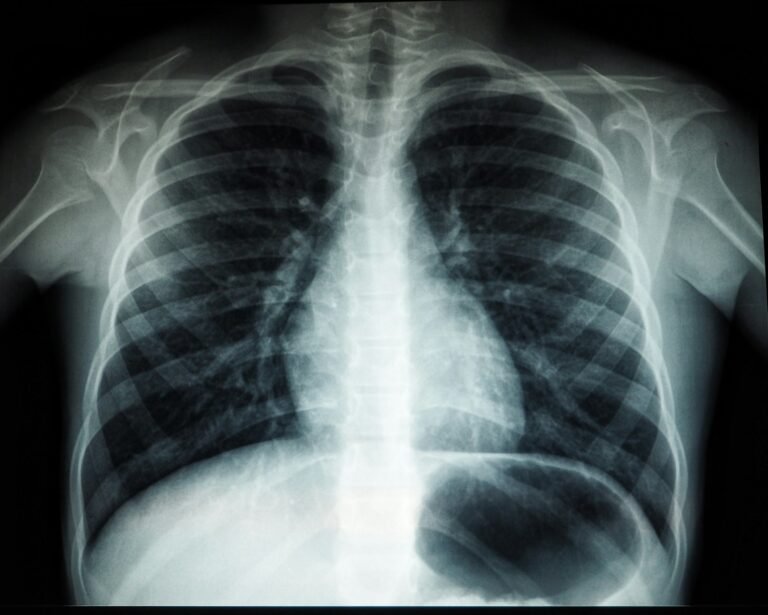

Día Mundial de la Radiología

El Día Mundial de la Radiología (también llamado International Day of Radiology) se celebra de manera anual desde el año …